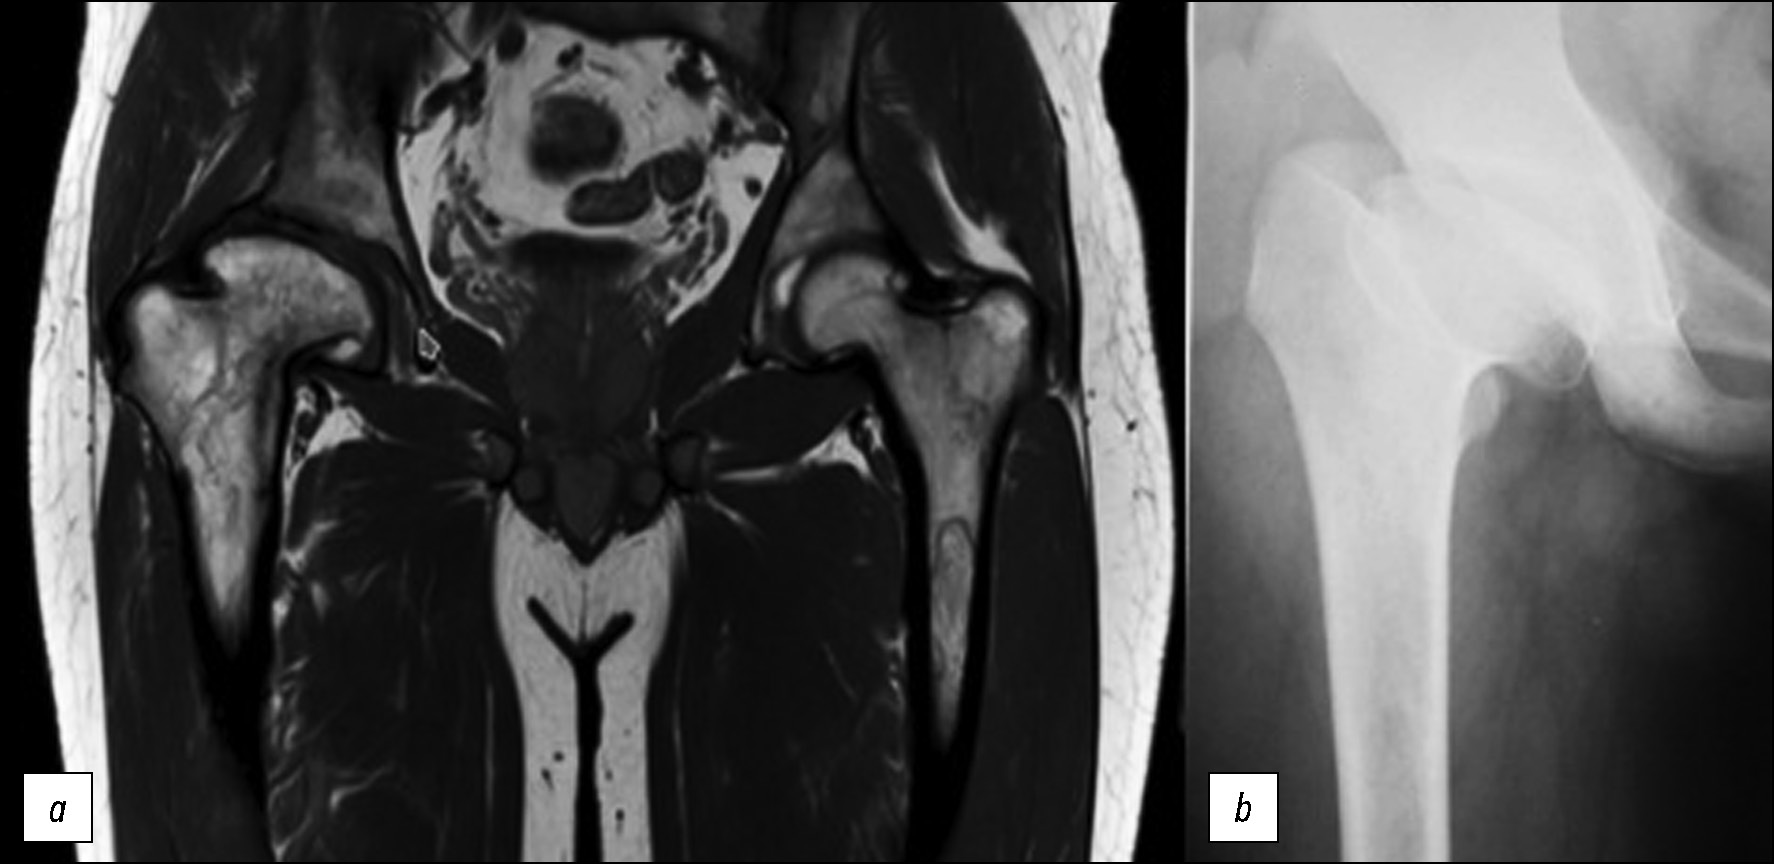

У 11 взрослых пациентов, перенёсших АНГБК в детском возрасте, сформировались изменения по типу coxa magna с типичным укорочением шейки бедренной кости и грибовидной деформацией головки. В 8 случаях мы наблюдали равномерную, нормальных размеров рентгенологическую суставную щель в сочетании с конгруэнтностью суставных поверхностей тазобедренного сустава (рис. 2). В клинической картине отсутствовал болевой синдром. Ограничения объёма движений отсутствовали либо были клинически незначимыми. Укорочение конечности поддавалось коррекции ортопедической обувью. Но у 3 пациентов с деформацией coxa magna во взрослом возрасте наблюдали вторичный коксартроз, потребовавший оперативного вмешательства.

Рис. 2. МРТ тазобедренных суставов: a — Т1-взвешенное изображение, корональная проекция, b — рентгенограмма правого тазобедренного сустава в прямой проекции. Деформация головки правой бедренной кости по типу coxa magna у взрослого пациента с болезнью Гоше, перенёсшего асептический некроз головки бедренной кости в детском возрасте.

Fig. 2. MRI of the hip joints: a — T1-WI, coronal projection, b — X-ray of the right hip. Right femoral head deformity of the coxa magna type in an adult patient with Gaucher disease who suffered osteonecrosis of the femoral head in childhood.